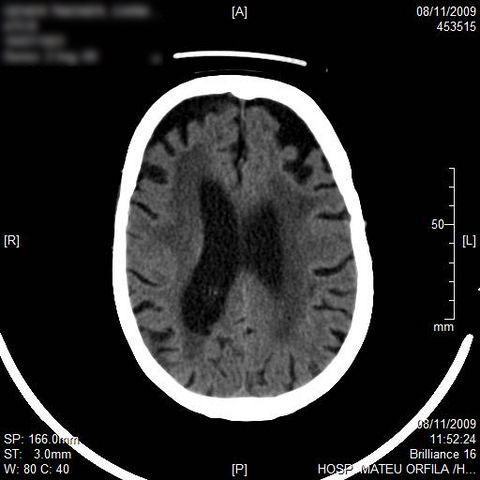

Hematoma subdural por caída.